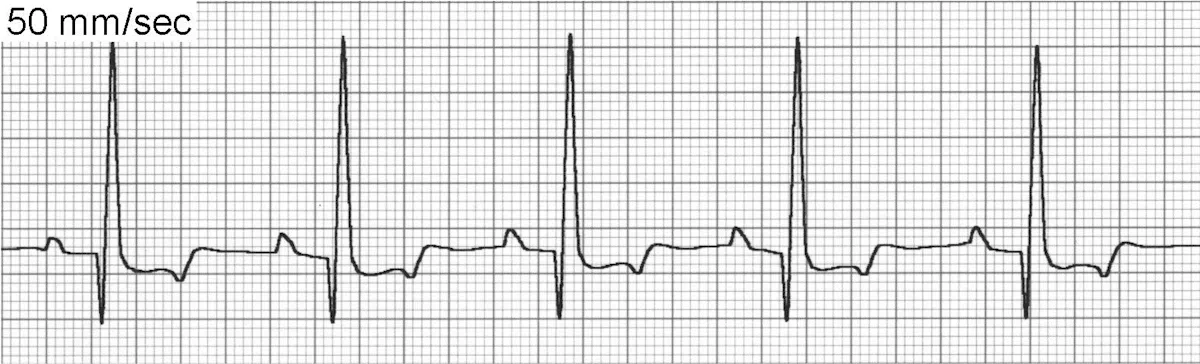

Sinus arrhythmia (Figure 3) is a phasic variation in heart rate in which R-R intervals often vary by >10%. There continues to be a P wave for every QRS complex and a QRS complex for every P wave, although on occasion the P wave morphology will vary or be difficult to visualize because of a phenomenon called wandering pacemaker (Figure 3B).

ECG of sinus arrhythmia

ECG of the wandering pacemaker phenomenon

Sinus arrhythmia is usually respiratory with the heart rate increasing in late inspiration and early expiration and decreasing in mid to late expiration. However, any other cause of increased vagal tone may also contribute to sinus arrhythmia even in the absence of respiratory variation. The underlying mechanism of sinus arrhythmia is depressed normal automaticity of the SA node.

Sinus arrhythmia is most common in normal resting dogs but uncommon in cats. Treatment is not required.